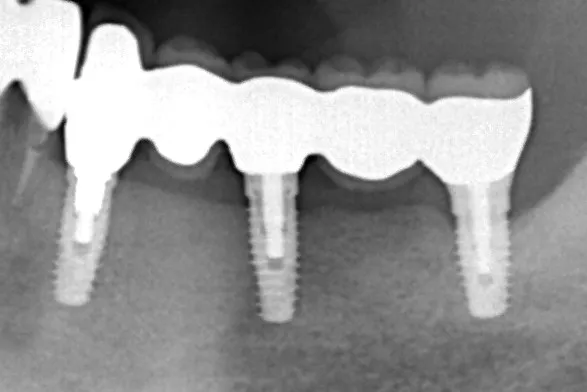

治療前

治療後

レントゲン画像

治療内容

左下5本欠損した部分をインプラント3本埋入して5本ブリッジで治したケースです。なかなかインプラントに踏み切れず、長い間入れ歯を使っておられましたが、噛みごたえがなく好きなものが食べれない上に、度々歯茎が痛んでは調整の繰り返しで快適に過ごすことができず、QOLの向上のためインプラント治療を決断されました。今ではなんでも食べれるとのことで、入れ歯で我慢しないでもっと早くインプラントにすればよかったと言っておられます。